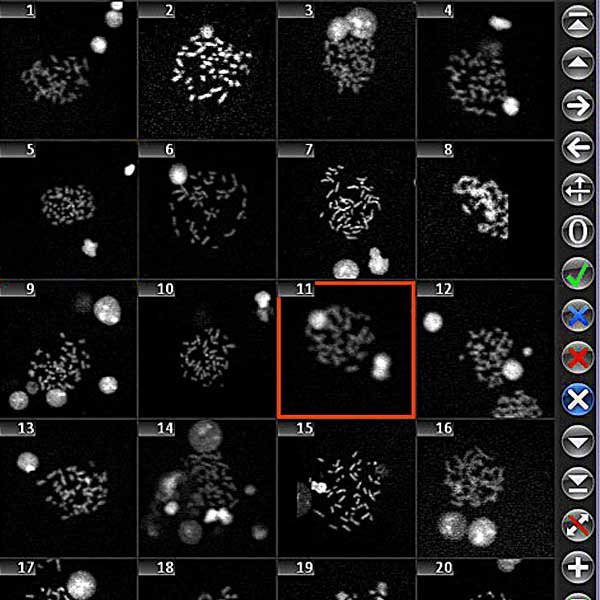

- Review all imaging results in a well-organized image gallery.

- Efficiently relocate identified objects on the microscope with a single mouse click.

Utilizing the Metafer software, imaging systems scan specimens of diverse sizes, employ various contrasting methods and magnifications, and identify, classify, and enumerate cells or other objects. Metafer's modularity and flexible architecture make it proficient in assisting users from various fields with their specific imaging tasks.

Given the variability of each microscopic sample, automated imaging demands flexibility. Metafer's distinctive concept provides an effective solution: user-trainable classifiers accurately establish imaging standards, and by selecting the relevant classifier, the integrated scanning system swiftly transitions to the next task.